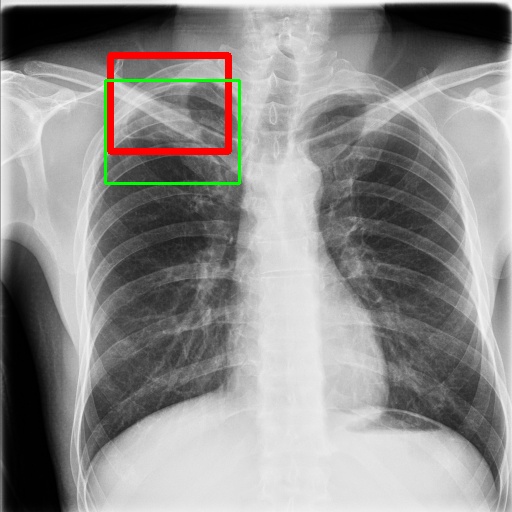

6.4 Visualization

To gain insights into the learning process of deep neural networks on CXR images, we visualize the feature map of SymFormer w/ RetinaNet at a scale of . To achieve this, we employ principal component analysis (PCA) to reduce the channels of the feature map to a single channel. The resulting single-channel map is then converted into a heat map for visualization purposes. The visualization of the learned features, along with the corresponding detection results, are presented in Fig. 6. Upon analysis, we observe that the visualization of healthy cases exhibits irregular feature patterns, indicating the absence of significant abnormalities. In contrast, the visualization of sick but non-TB cases displayed some discernible highlights, potentially representing the presence of lesions. For TB cases, the highlights in the visualization map align well with the annotated TB infection areas, thereby indicating the effectiveness of the proposed SymFormer in learning deep features for TB area detection. Furthermore, in Fig. 7, we offer qualitative comparisons between the proposed SymFormer and the baseline models for TB infection area detection. As evident, SymFormer consistently delivers superior qualitative detection results.